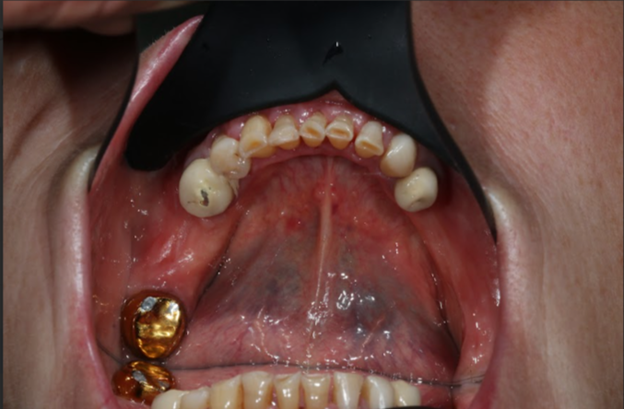

Елена Борисовна пришла с жалобами на отсутствие некоторых зубов, старенькие коронки. Стертость металлической коронка до основания металла коронки. Это, коронка с напылением не титана, поэтому напыление стирается до металлического оттенка. Также большую площадь стираемости своих зубов.

В клинике «Практика доктора Склярука» провели 3D диагностику, компьютерную диагностику, сканирование верхней и нижней челюсти.

После, было принято решение подойти к вопросу преображения комплексно и начать с проф. гигиены полости рта.